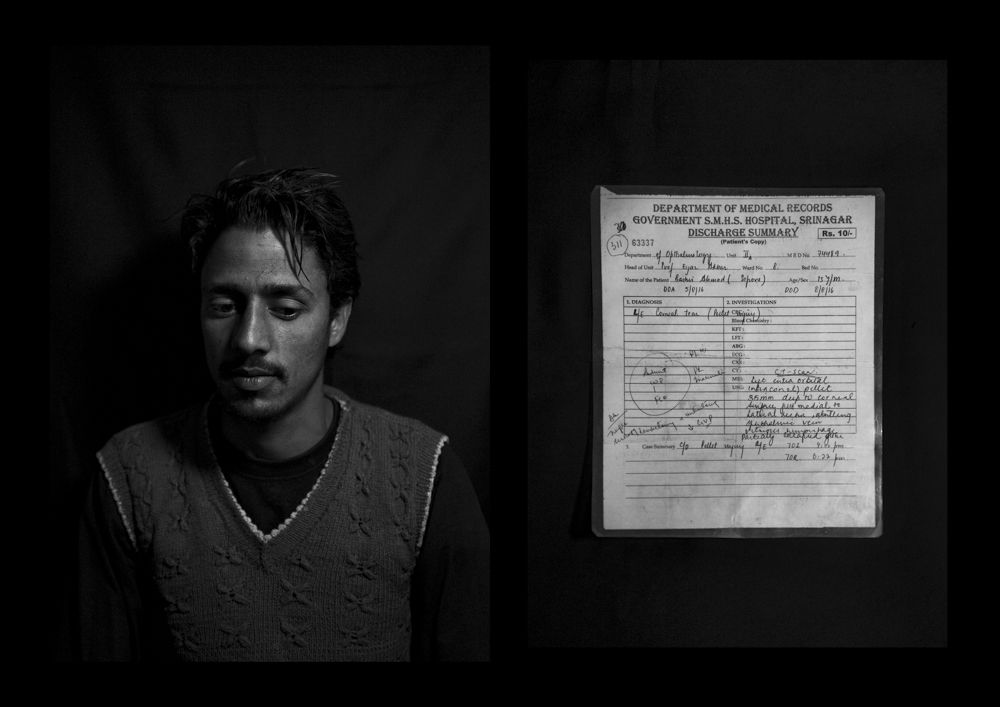

The valley of Kashmir, disputed by India and Pakistan since 1947, is one of the most militarized zones in the world.

In the last years, the Indian government provided the security forces deployed with a new weapon: a shotgun that fires hundreds of metal pellets to keep the urban protests under control. Defined as “non-lethal”, according to a UN report released in 2018, the weapon is responsible for blinding around 1000 people.

Left partially or totally blind, victims speak of the darkness descended upon their lives. The only things left to see are the faint shadows that surround them.